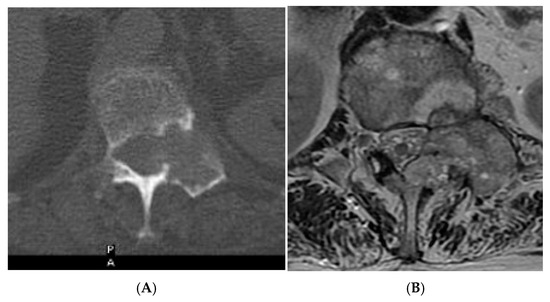

Figure 13.

Aggressive spine haemangioma. (A) Axial CT showing lytic lesion within the left-side posterior aspects of the vertebral body with cortical destruction. (B) Axial T2W MRI with the expansile lesion encroaching within the spinal canal and neural foramen. (C) Sagittal T1W MRI. (D) Sagittal T2W MRI and (E) sagittal STIR MRI, demonstrating a more vascular component of the lesion along with expansile component effacing the neural foramen.